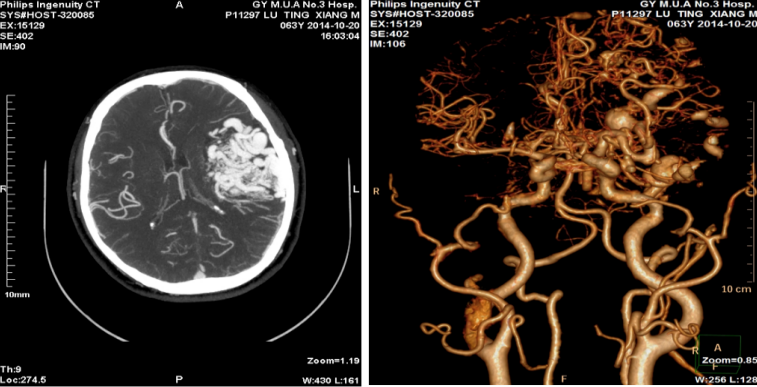

对经常“头昏、头痛”且既往无高血压疾病的患者,可提供头颈部CTA检查,从而早期发现是否有头颈部血管硬化、狭窄及畸形等问题导致头昏、头痛。

图为脑血管畸形案例